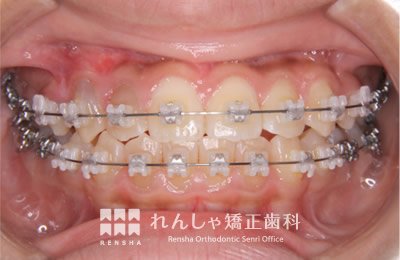

中高生

永久歯列はほぼ完成してしますが、歯列を側方だけでなく後方へも拡大し、埋まっていた右上奥歯を引っ張り出しています。

| 主訴 | 埋まったままでてこない歯がある |

|---|---|

| 診断名 | Angle Class II 小臼歯の埋伏と叢生を伴う上顎前突 |

| 初診時年齢 | 13歳5か月 |

| 装置名 | マルチブラケット装置 |

| 抜歯非抜歯 | 非抜歯 |

| 治療期間 | 2年3か月 |

| 費用の目安 | 約82万円+消費税(検査料金、都度の処置費用等も合わせた総額) |

| リスク副作用 | 歯の移動に伴う軽微な歯根吸収、歯槽骨吸収、歯肉退縮(本症例では軽度の歯根吸収を認めた)、矯正器具装着中のカリエスリスク増大(本症例ではカリエス発生無し) |